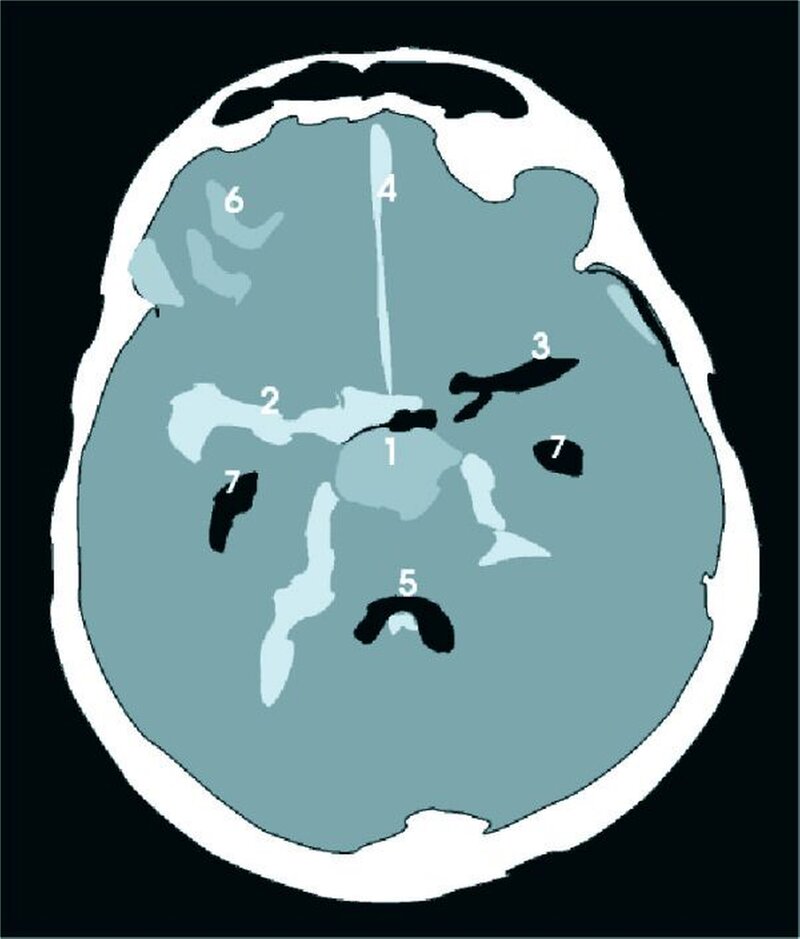

Nach Aufnahme und Abklärung in der neurologischen Abteilung lautet die Diagnose: Transitorisch Ischämische Attacke (TIA) bei hochgradiger Stenose der rechten A. carotis interna. Bei der TIA handelt es sich um eine zerebrale Durchblutungsstörung (Tabelle). Diese verursacht eine vorübergehende neurologische Störung, die in ihren Symptomen einem Schlaganfall gleicht, sich aber wieder vollständig zurückbildet. Eine TIA dauert wenige Minuten bis Stunden (definitionsgemäß maximal 24 h). Überdauert die neurologische Symptomatik den Zeitraum von 24 Stunden, handelt es sich definitionsgemäß um ein Prolongiertes Reversibles Ischämisches Neurologisches Defizit, kurz PRIND. Diese Einteilung ist zurzeit jedoch Gegenstand kontroverser Diskussionen. Im akuten Stadium ist eine Unterscheidung zwischen TIA und Schlaganfall nicht möglich.

Der Überbegriff „Schlaganfall“ umfasst zwei Krankheitsbilder. Zum einen den primär ischämischen Infarkt, verursacht durch eine plötzlich auftretende Minderdurchblutung, zum anderen die akute Hirnblutung, die sekundär durch ihre raumfordernde Wirkung oder durch die mangelnde Durchblutung nachfolgender Areale ebenfalls zu einer Ischämie führt.

Die Symptome, analog der Pathologie, entsprechen denen des Schlaganfalls. Typische Symptome treten je nach betroffenem Hirnareal auf: Bei einer Durchblutungsstörung im Karotisstromgebiet treten typischerweise eine Amaurosis fugax (reversible, Sekunden bis wenige Minuten andauernde, meist einseitige Blindheit), Störungen der Sprache (wie Wortfindungsstörungen, gestörte Artikulation), Hemiparesen, Hemihypästhesien und Fazialisparesen auf. Auf eine Durch- blutungsstörung der A. vertebralis oder der A. basilaris weisen Gleichgewichtsstörungen mit und ohne Schwindel, Schluckstörungen, Hörstörungen, Sprechstörungen, Tetraparesen und halb- beziehungsweise doppelseitige Sensibilitätsstörungen hin.